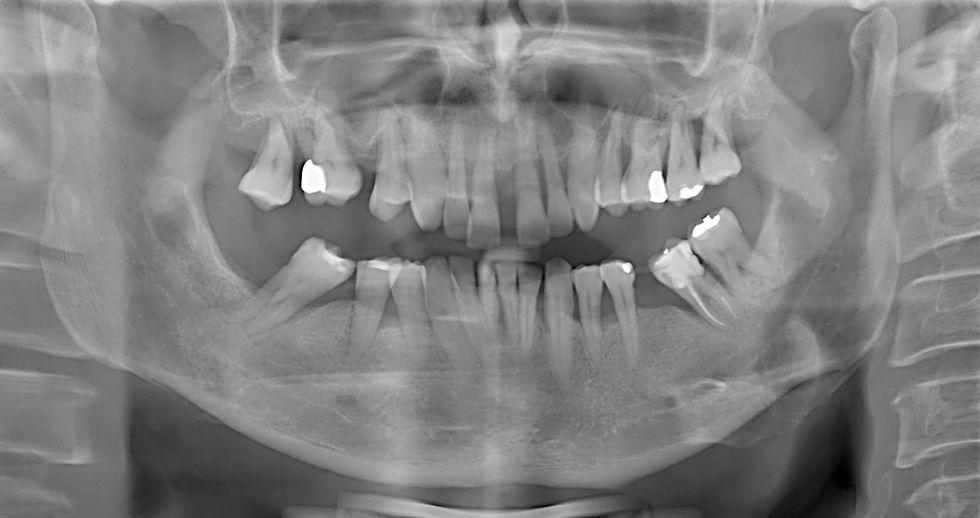

Initial radiographic control.